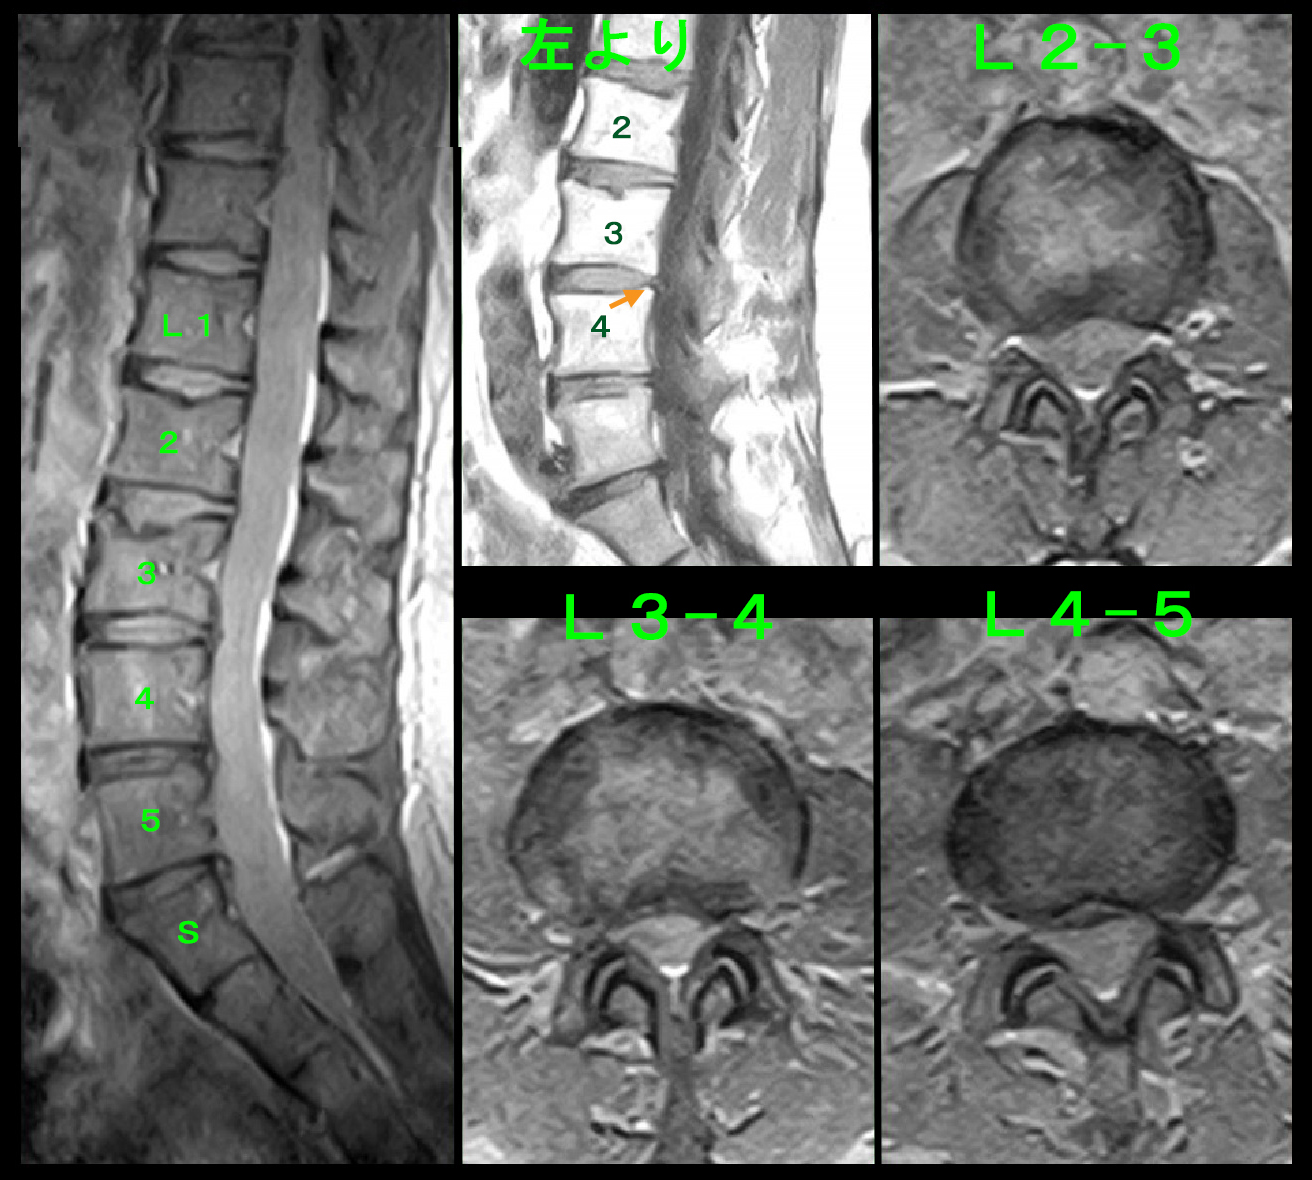

54才女 MR1.jpg

腰椎MRI検査でも目立った所見は確認されませんが、L23・L34・L45・L5Sの各椎間板に軽度の椎間板ヘルニアが確認されました。どこの椎間板が明確に脊髄を圧迫していて、それが坐骨神経痛の原因であろうと推察できません。しかし、医師は原因を見つけ出さなければなりません。そのような場合、私は4分割の左上のT1矢状断の画像のオレンジ矢印で示すL34の椎間板の突出が他の椎間板に比して白っぽくなっていると評価しました。私はT1の椎間板の突出部位が白い場合、そこが最近悪化した箇所であると判断しているので、Yさんの病因はL34の椎間板ヘルニアであろうと判断し、左L4神経根ブロックを施行しました。